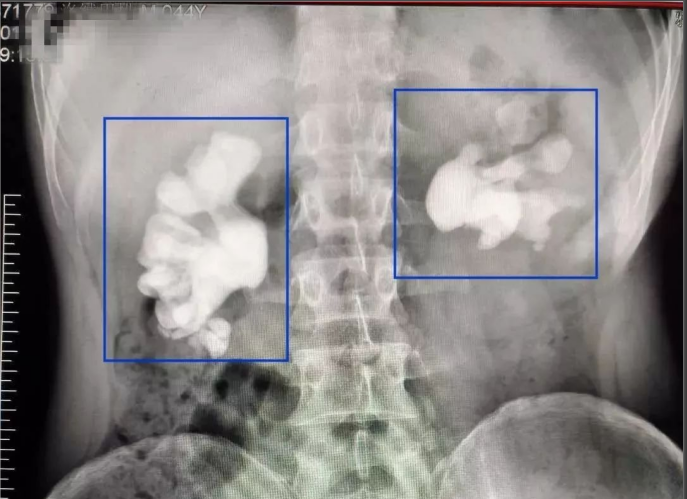

進(jìn)一步通過(guò)X線照片檢查發(fā)現(xiàn)雙腎鑄型結(jié)石,右腎盂內(nèi)有大小約11厘米的結(jié)石,其形狀如同“老生姜”,整個(gè)右腎盂和所有腎盞腔隙都被結(jié)石填滿,左側(cè)并有嚴(yán)重積液及泌尿道感染。患者的左側(cè)腎臟腎功能所剩無(wú)幾,更為嚴(yán)重的是化驗(yàn)結(jié)果顯示患者總體腎功能已出現(xiàn)衰竭,臨床上已出現(xiàn)輕度貧血等腎衰竭的癥狀,如不及時(shí)診治,病人不可避免的要發(fā)展成為尿毒癥,后果非常嚴(yán)重!

“這樣巨大的結(jié)石在臨床十分罕見(jiàn),估計(jì)得二十來(lái)年才能長(zhǎng)成這么大。”醫(yī)生驚嘆道。這個(gè)結(jié)石的大小也突破了雅安仁康醫(yī)院收治鑄型結(jié)石的紀(jì)錄。

腎結(jié)石,鑄狀結(jié)石

雙腎鑄狀結(jié)石